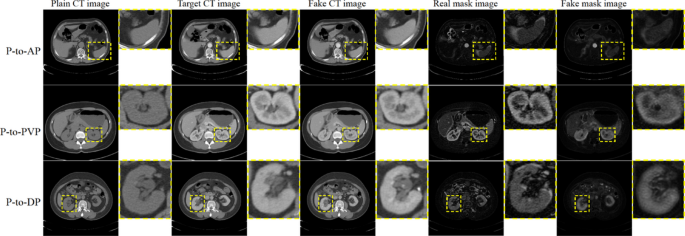

To visualize the generated mask images, Fig. 4 shows the mask images for different phases of CT translation. In P-to-AP translation, the fake mask image tends to enhance the liver regions as does the real mask image. When translating from plain to PVP CT images, the regions of the kidney are contrast-enhanced in both the real and fake mask images, indicating that MaskNet can capture contrast-enhanced regions as accurately as the subtraction technique can.

The visual results of mask images for P-to-AP, P-to-PVP and P-to-DP translation on Dataset 1.